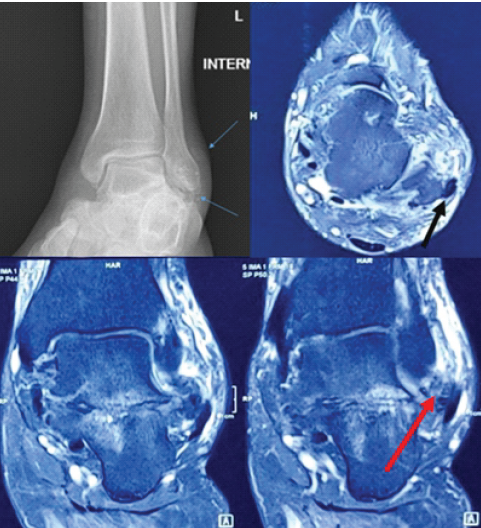

A 37-year-old male presented at our clinic with a history of pain over the lateral side of the left ankle for 3 months. He had no history of trauma. Physical examination revealed a mild prominence arising from the posterolateral aspect of the distal fibula, and there was demonstrable peroneal tendon instability on ankle movements (Fig 1). Ankle anteroposterior and lateral radiographs showed multiple small calcified lesions near the lateral malleolus (Fig 2).

Figure 2: X-ray showing distal fibula lesion. Magnetic resonance imaging shows the osteochondroma (red arrow) and peroneal subluxation (black arrow).

Magnetic resonance imaging revealed peroneal tendon subluxation anteriorly and a bony lesion present in the distal fibula and the lateral aspect of the calcaneum. We proceeded with surgery to explore the bony mass and peroneal tendons. Surgery was performed in the theater. The patient was given intravenous antibiotics, and surgery was carried out under a thigh tourniquet at 300 mmHg. A lateral incision was made over the distal fibula, we found subluxed peroneal tendons with absent superior peroneal retinaculum (SPR) and peroneal groove (Fig. 3). We also uncovered an osteochondroma of size 2.5 × 2.5 × 2 cm at the distal end of fibula and another bony exostosis of size 1.5 × 1.5 × 1.5 from lateral aspect of calcaneum (Fig. 3).